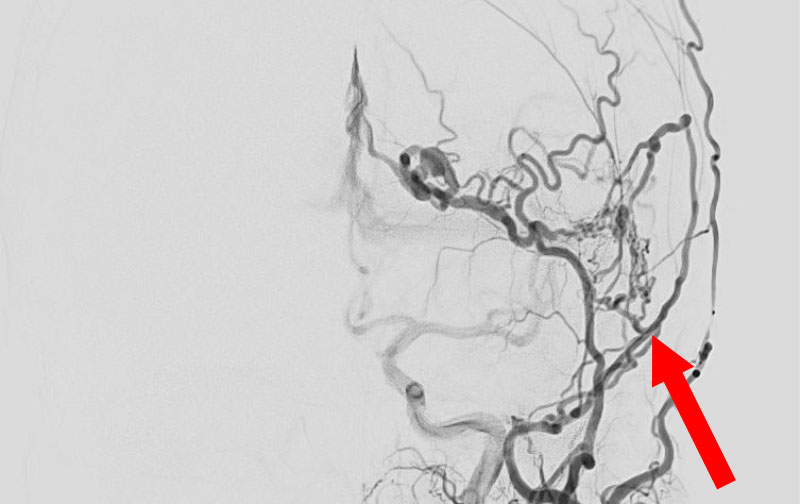

1586

'25年10月6日

硬膜動静脈瘻

40代

大阪府の病院

後

手術日